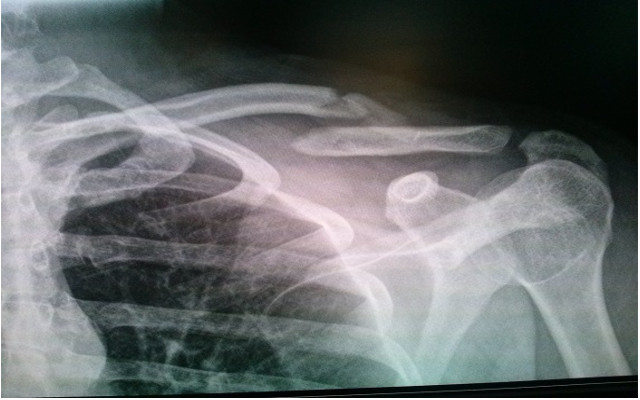

El siguiente es un caso A. Paciente de 26 años que practica deportes, llega a la unidad de emergencia de uno de nuestros centros hospitalarios en el país y colocan un vendaje en 8, B. el paciente en control radiográfico con su vendaje 15 días después, se evidencia el desplazamiento y lo poco útil del vendaje, además de los problemas antes mencionado que le provoca al paciente.